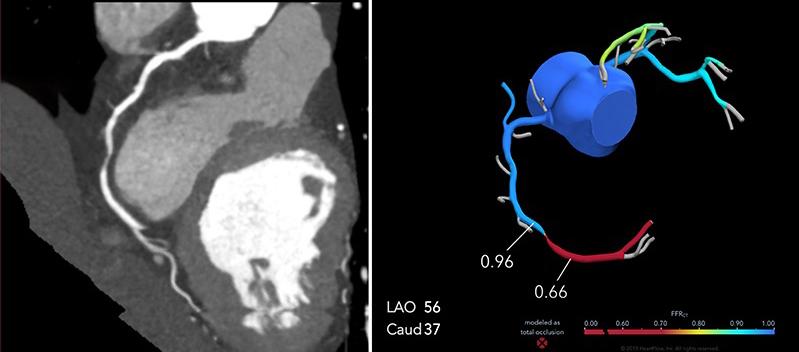

Estáequipadoconunagrancantidadde aplicacionessofisticadasqueabarcan especialmenteestudioscardiovasculares:Se puedeevaluarelcorazón,analizarmediante angiotomografíacoronariasusarteriasyrea‐lizarprotocolosparapacientesaquienesse lesplanearealizarunreemplazovalvular.Tie‐neunaresoluciónespacialquebrindamejor definicióndeimagenenestudioscomo angiotomografíademiembrospélvicos, angiotomografíaaórtica,angiotomografía cerebral,angiotomografíadetroncossupra‐aórticos,loquepermitediagnosticaryplanifi‐carlosprocedimientosencasoscomoaneu‐rismas,estenosisoanomalíasvasculares. Cuentaconherramientasfuncionalescomo perfusióncerebralyesposiblerealizarestu‐dioscomotomografía,colonoscopíavirtual, enteroUrotomografía.

Actualmentesoyelúnicoradiólogo intervencionistaenelestadodeColima.La radiologíaintervencionistaesunasu‐bespecialidaddelaradiologíaqueseencarga derealizarprocedimientosdiagnósticosy terapéuticosdemínimainvasión.Estaabarca unamplioespectrodeenfermedadesque puedenserresueltasmedianteestastécnicas.

Lasangiografíasdiagnósticasnosayudana analizarlaanatomíadelasarteriasyvenas quellevanlasangrealosórganos,comolo sonelcerebro,lasextremidadesoelintestino. Enocasionessepuederealizarenunmismo procedimientoeltratamiento,comoangiopla‐stiasenelcasodeestrechezdelasarteriasa niveldelaspiernasoembolizaciones,que consistenentaparelflujodesangrecuando presentamalformacionesenlosvasosoaen pacientesconsangradoactivo,como,por ejemplo,enelintestino.